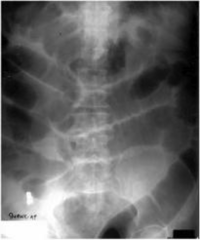

Bowel Obstruction

Bowel Obstruction Description- both the small and large bowels are nearly always active in peristalsis Mechanical Bowel Obstruction Description-one in which the lumen of the bowel becomes occluded due to trapped hernia, tumors, volvulus, intussusception, crohn's disease, appendicitis Etiology- most often occurs postoperatively from adhesions Signs and symptoms- vomiting with bile, abdominal distention, and pain Diagnosis- sequential radiographs taken over 12-24 hours show gas in small bowel with multiple air/fluid levels. Erect/Decubitus films show step ladder appearance Treatment- decompression of the intestine to remove gas and surgery to remove the causative agent

What type of appearance does paralytic ileus typically take on a radiograph

step ladder appearance

Paralytic Ileus

Description- FAILURE OF NORMAL PERISTALSIS Etiology- most commonly occurs following surgery and intraperitoneal or retroperitoneal infection. Adynamic ileus. Certain drugs can cause this. Signs & Symptoms- Abdominal pain, diarrhea, VOMITING WITHOUT NAUSEA Diagnosis- Abdomen radiograph. Intestinal gas/fluid on films. Step ladder appearance. Treatment- MEDICAL STIMULATION OF THE BOWEL TO RESTORE PERISTALSIS.